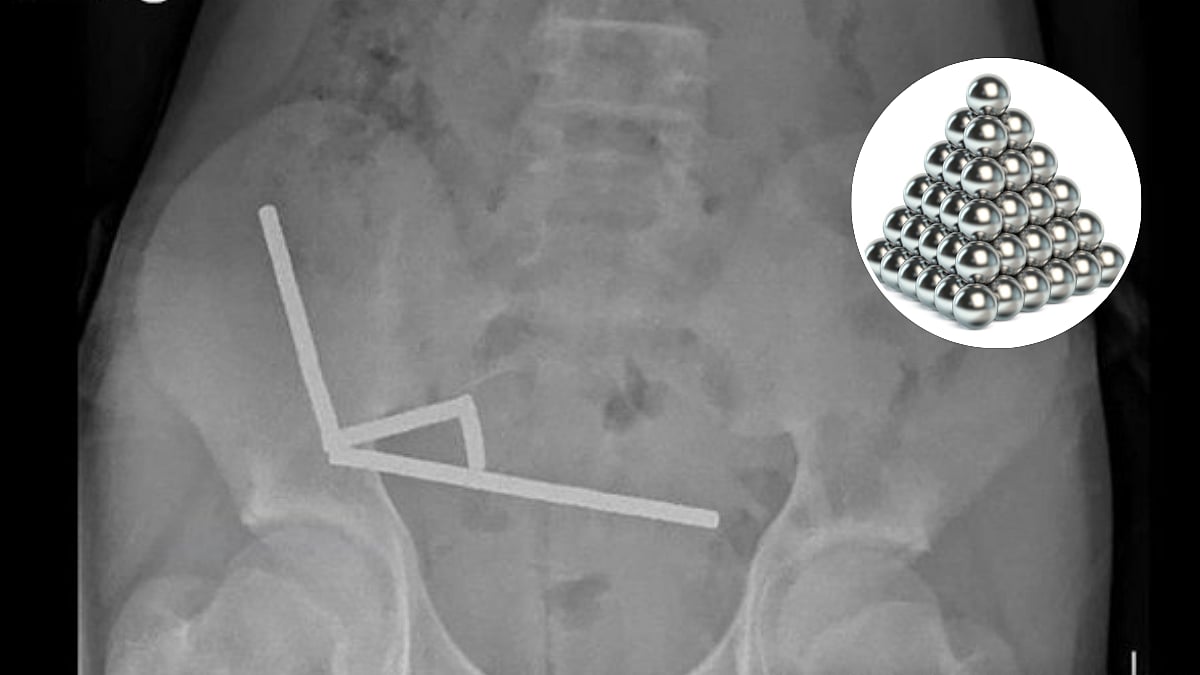

In a shocking incident from New Zealand, a 13-year-old boy had to undergo a tricky surgery after he swallowed dozens of highly powered magnets purchased from an e-commerce marketplace on the Internet. Doctors had to remove a portion of his intestine to recover all the magnets.

The disturbing event came even after the country had prohibited the selling of small, powerful magnets for domestic or personal use since 2014, when the child swallowed up to 100 of them that he had ordered from Temu, a popular online marketplace.

Surgeons at the Tauranga Hospital wrote in the New Zealand Medical Journal that the teen boy swallowed around 80 to 100 small magnets a week before the surgery. He had purchased them on Temu.

"He disclosed ingesting approximately 80–100 5x2mm high-power (neodymium) magnets about one week prior, which were purchased from an overseas online marketplace (Temu)."